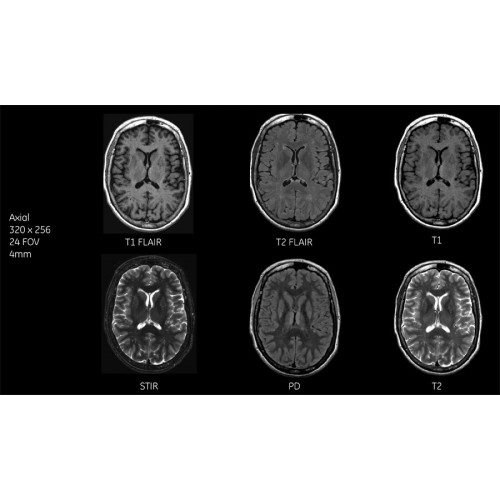

Система SIGNA Pioneer воплощает поразительные достижения в области визуализации. Передовая технология Total Digital Imaging (TDI) позволяет добиться большей четкости изображений и на четверть повысить соотношение сигнал/шум.

TDI построена на трех базовых компонентах:

• Технология Direct Digital Interface (DDI) использует независимый аналого-цифровой преобразователь для оцифровки сигнала от каждого из 97 радиочастотных каналов, что обеспечивает значительное увеличение качества за счет уменьшения фонового шума.

• Технология Digital Micro Switching (DMS) — это следующее поколение технологий радиочастотных катушек, основанное на замене аналоговых схем блокировки сверхбыстрыми микропереключателями (MEMS), что делает возможным быстрое переключение катушек для дальнейшего расширения возможностей визуализации с нулевым TE.

• Технология Digital Surround Technology (DST) — это новая технология объемной оцифровки данных, объединяющая сигналы от каждого элемента катушки. Прекрасное соотношение сигнал/шум и чувствительность поверхностных катушек в сочетании с превосходной однородностью и высокой проникающей способностью встроенной радиочастотной катушки — все это позволяет создавать качественные изображения не только позвоночника, но и всего тела.

Помимо технологии 97 РЧ-каналов, SIGNA Pioneer использует магнит 3.0Т высокой однородности, предназначенный для повышения качества визуализации во всех областях, а также закладывающий прочный фундамент для долгосрочных инвестиций и роста клинических возможностей.

Благодаря революционному программному пакету Silent Suite уровень шума снижается до 77 дБ, что всего на 3 дБ выше уровня окружающей среды. Программный пакет Silent Suite теперь включает полный пакет приложений для исследования ЦНС (T1, T2 FLAIR, DWI10, МРА). Кроме того, мы расширили возможности визуализации Silent за пределы ЦНС для исследований скелетно-мышечной системы и позвоночника. Silent Suite – платформа, содержащая в себе все импульсные последовательности для бесшумного сканирования.